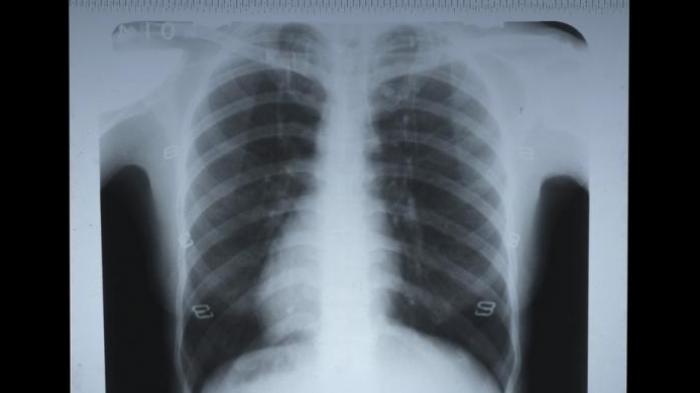

Setelah diperiksa, dokter yang bersangkutan menganjurkan dirontgen untuk melihat gigi bungsu saya yang baru tumbuh dan letaknya agak miring.